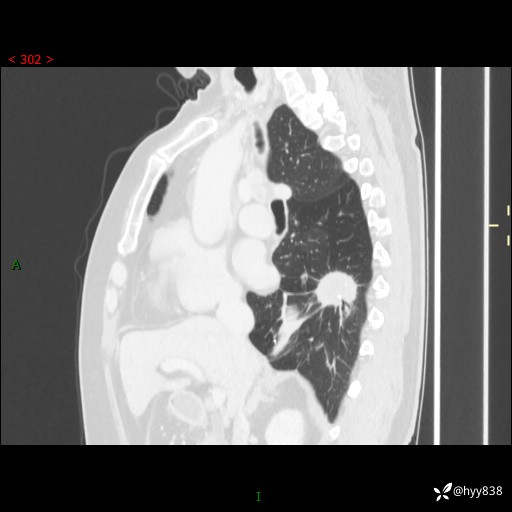

胸部CT肺窗(平扫外院)